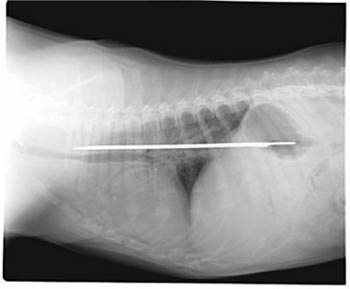

This photo of an X-Ray provided by Imperial Point Animal Hospital in Fort Lauderdale, Fla., Saturday, Sept. 24, 2005, shows a 13-inch serrated knife that somehow was swallowed by 'Elsie' a 6-month-old Saint Bernard puppy. [AP]

Elsie, a Saint Bernard puppy, apparently had the blade between her esophagus and stomach for about four days before it was removed earlier this week in a 2-hour operation.

The puppy has an 8-inch scar, but is fine and back with her family. And the knife is back in Scarola's kitchen, albeit this time wrapped in a towel and placed in a cabinet atop the refrigerator.